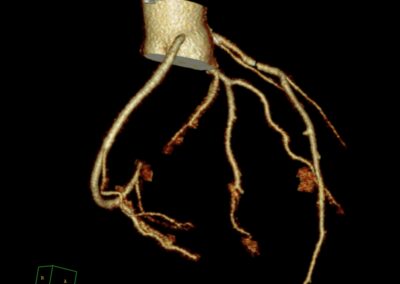

Τρισδιάστατη και δισδιάστατη απεικόνιση των στεφανιαίων αγγείων όπου διακρίνεται σημαντική στένωση λίγο μετά την έκφυσή του πρόσθιου κατιόντα κλάδου